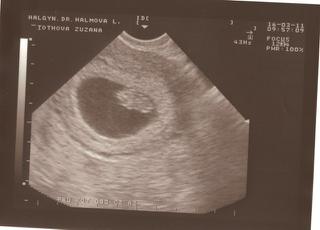

Tu sú sľúbené fotky 🙂

@santerra bábo sa hýbalo, lekárka ma na to upozornila viac krát, ale bolo to pekne vidieť, srdiečko tiež krásne bilo a fotky sa snažím nahodiť, len sa mi sem akosi nechcú nahrať nechápem prečo.....ešte skúsim zmeniť veľkosť.